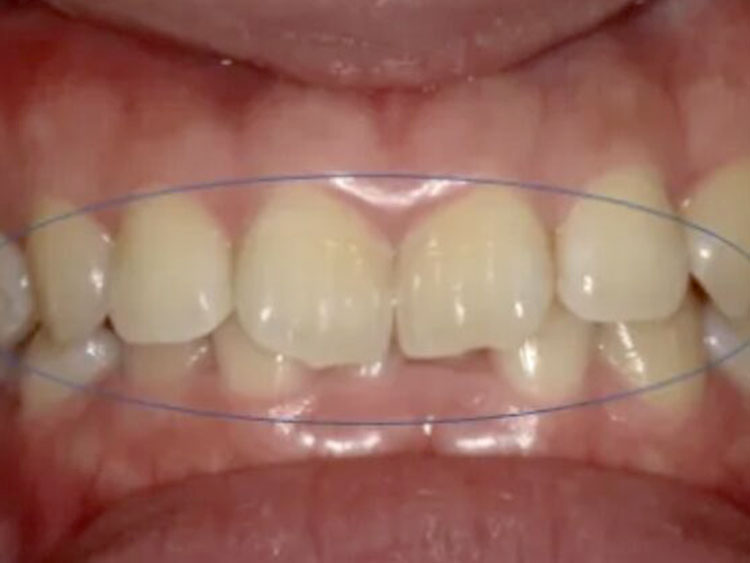

20代。 「前歯の傾きが気になる」「下の歯のガタつき」を主訴に来院。 検査の結果、上の前歯が下の前歯を深く覆ってしまう「過蓋咬合(Deep Bite)」の状態であり、見た目だけでなく噛み合わせの機能改善も必要でした。